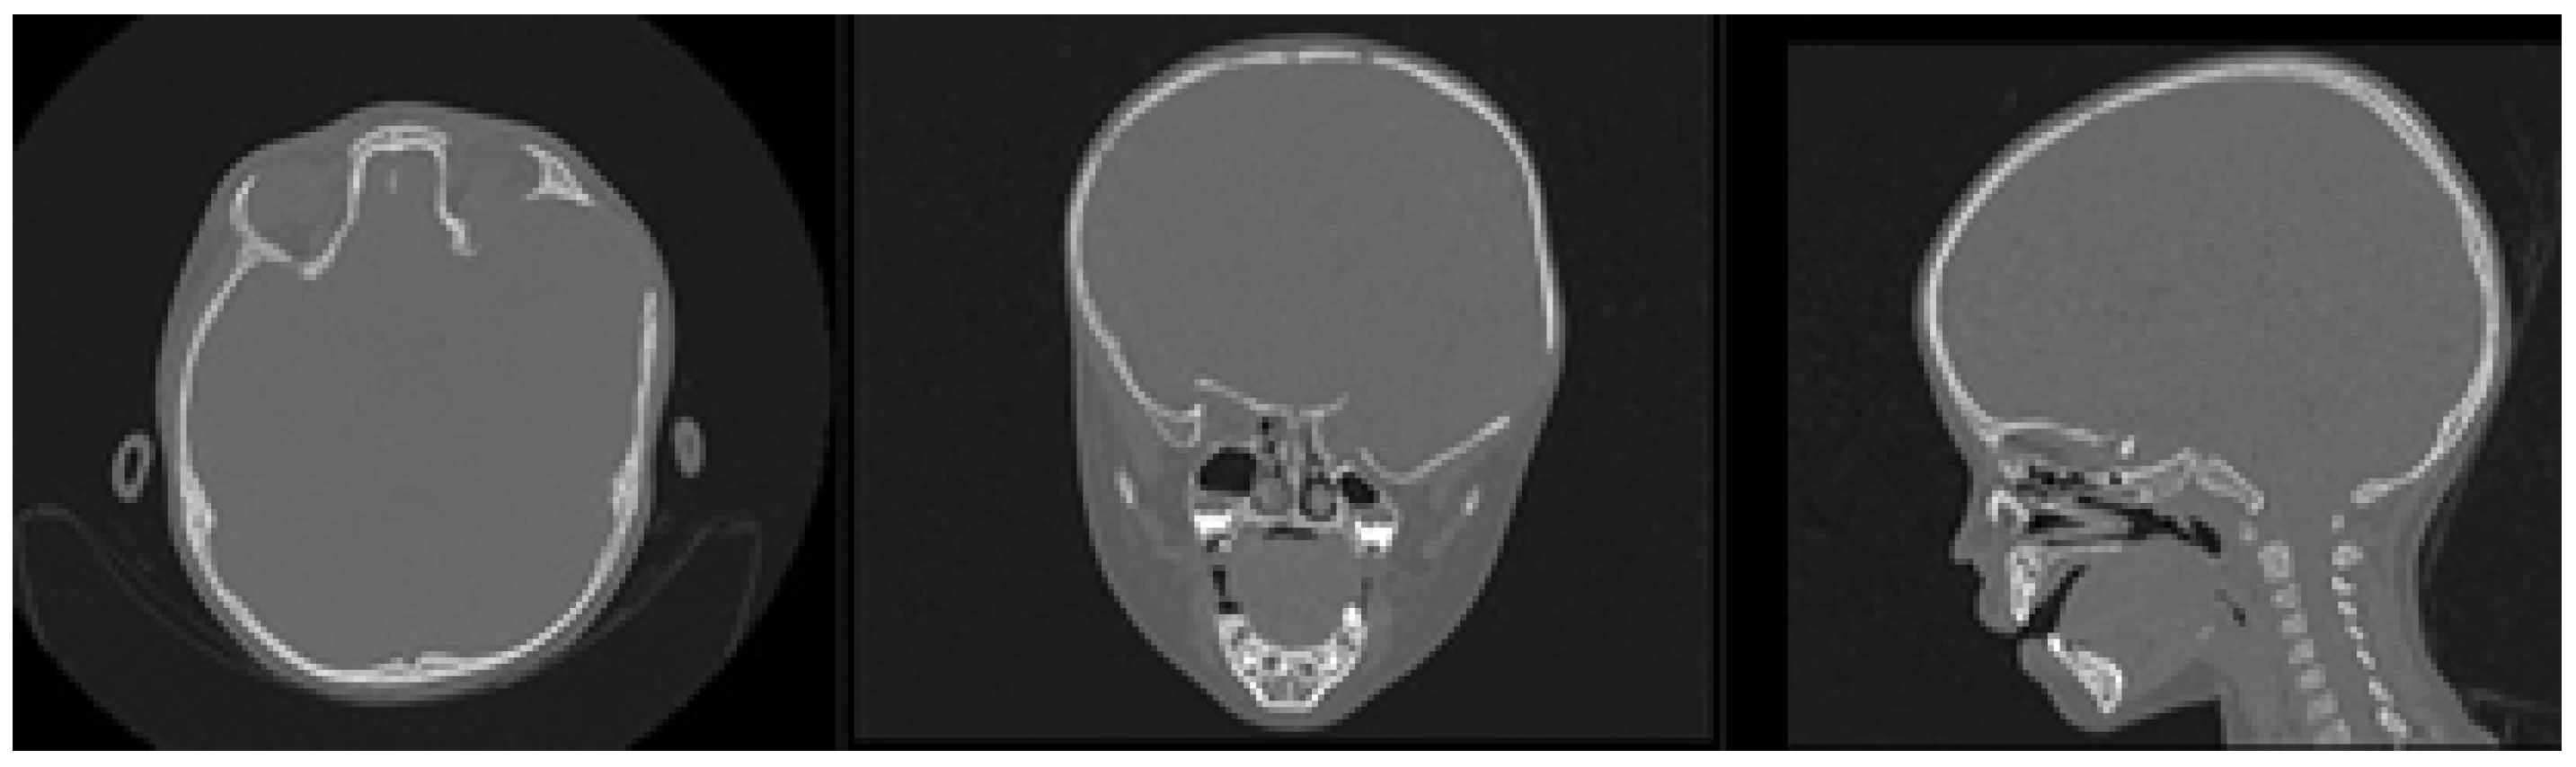

The patient was a 10-year-old male who sustained a cranial collapse in the left temporal-parietal-occipital region. This is a sequelae of cranioencephalic trauma, with multiple surgical interventions having been performed. A physical examination was conducted, which revealed subsidence in the temporo-parieto-occipital region, accompanied by some scars. Cerebral activity manifests itself externally, as evidenced by the visible transmission of light from the brain to the skin (see Figure 10). Upon tactile examination, the irregular edges of a bone defect resulting from an anterior craniotomy were palpable. A CT scan with 3D reconstruction was performed, where the solution of bone continuity in the affected area can be seen (Figure 11).

Reconstruction of the defects found, both in the anamnesis and in the physical and radiological examinations, was performed applying 3D digital restoration (Figure 12) and manufacturing of the anatomical test models with the help of stereolithography.

Figure 11. TAC: sinking in the temporo-parieto-occipital region (left). Solution of bone continuity in the affected area (centre-right).

Figure 12. Bone segmentation of the anatomical model from the tomographic image.

Figure 13. Three-dimensional anatomical model of the skull and non-implantable prosthesis (only for planning).